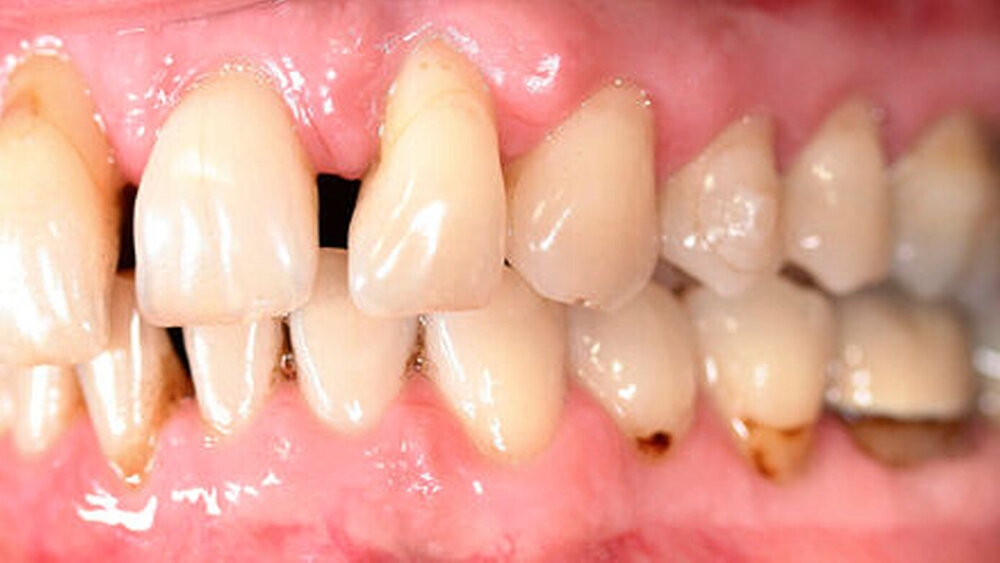

Anamnestisch lagen keine Besonderheiten vor. Es ist jedoch zu vermerken, dass ein regelmäßiger Alkohol-, Koffein- und Nikotinkonsum zugrunde lag. Intraoral zeigte sich ein bereits konservierend versorgtes permanentes Gebiss mit aktivem und inaktivem kariösen Geschehen. Große Anteile der Zahnhälse lagen nach Zahnfleischrückgang in Kombination mit Knocheneinbrüchen frei. Zahn 27 wurde bereits extrahiert.

Eine Beurteilung der parodontalen Situation an Zahn 11 offenbarte mesial und distal Sondierungstiefen von jeweils 6 mm.

Röntgenologisch stellte sich im Orthopantomogramm der bereits intraoral ersichtliche horizontale und vertikale Knochenabbau mit Attachmentverlust an einzelnen Zähnen dar. Die Erhaltungswürdigkeit einzelner Zähne war aufgrund des starken Knochenverlustes beziehungsweise der Beeinträchtigung des Halteapparates als kritisch zu beurteilen.

Zudem wurde die Diagnose einer Parodontitis gestellt, die eine Rücküberweisung an den Hauszahnarzt erforderlich machte (Abbildung 2).